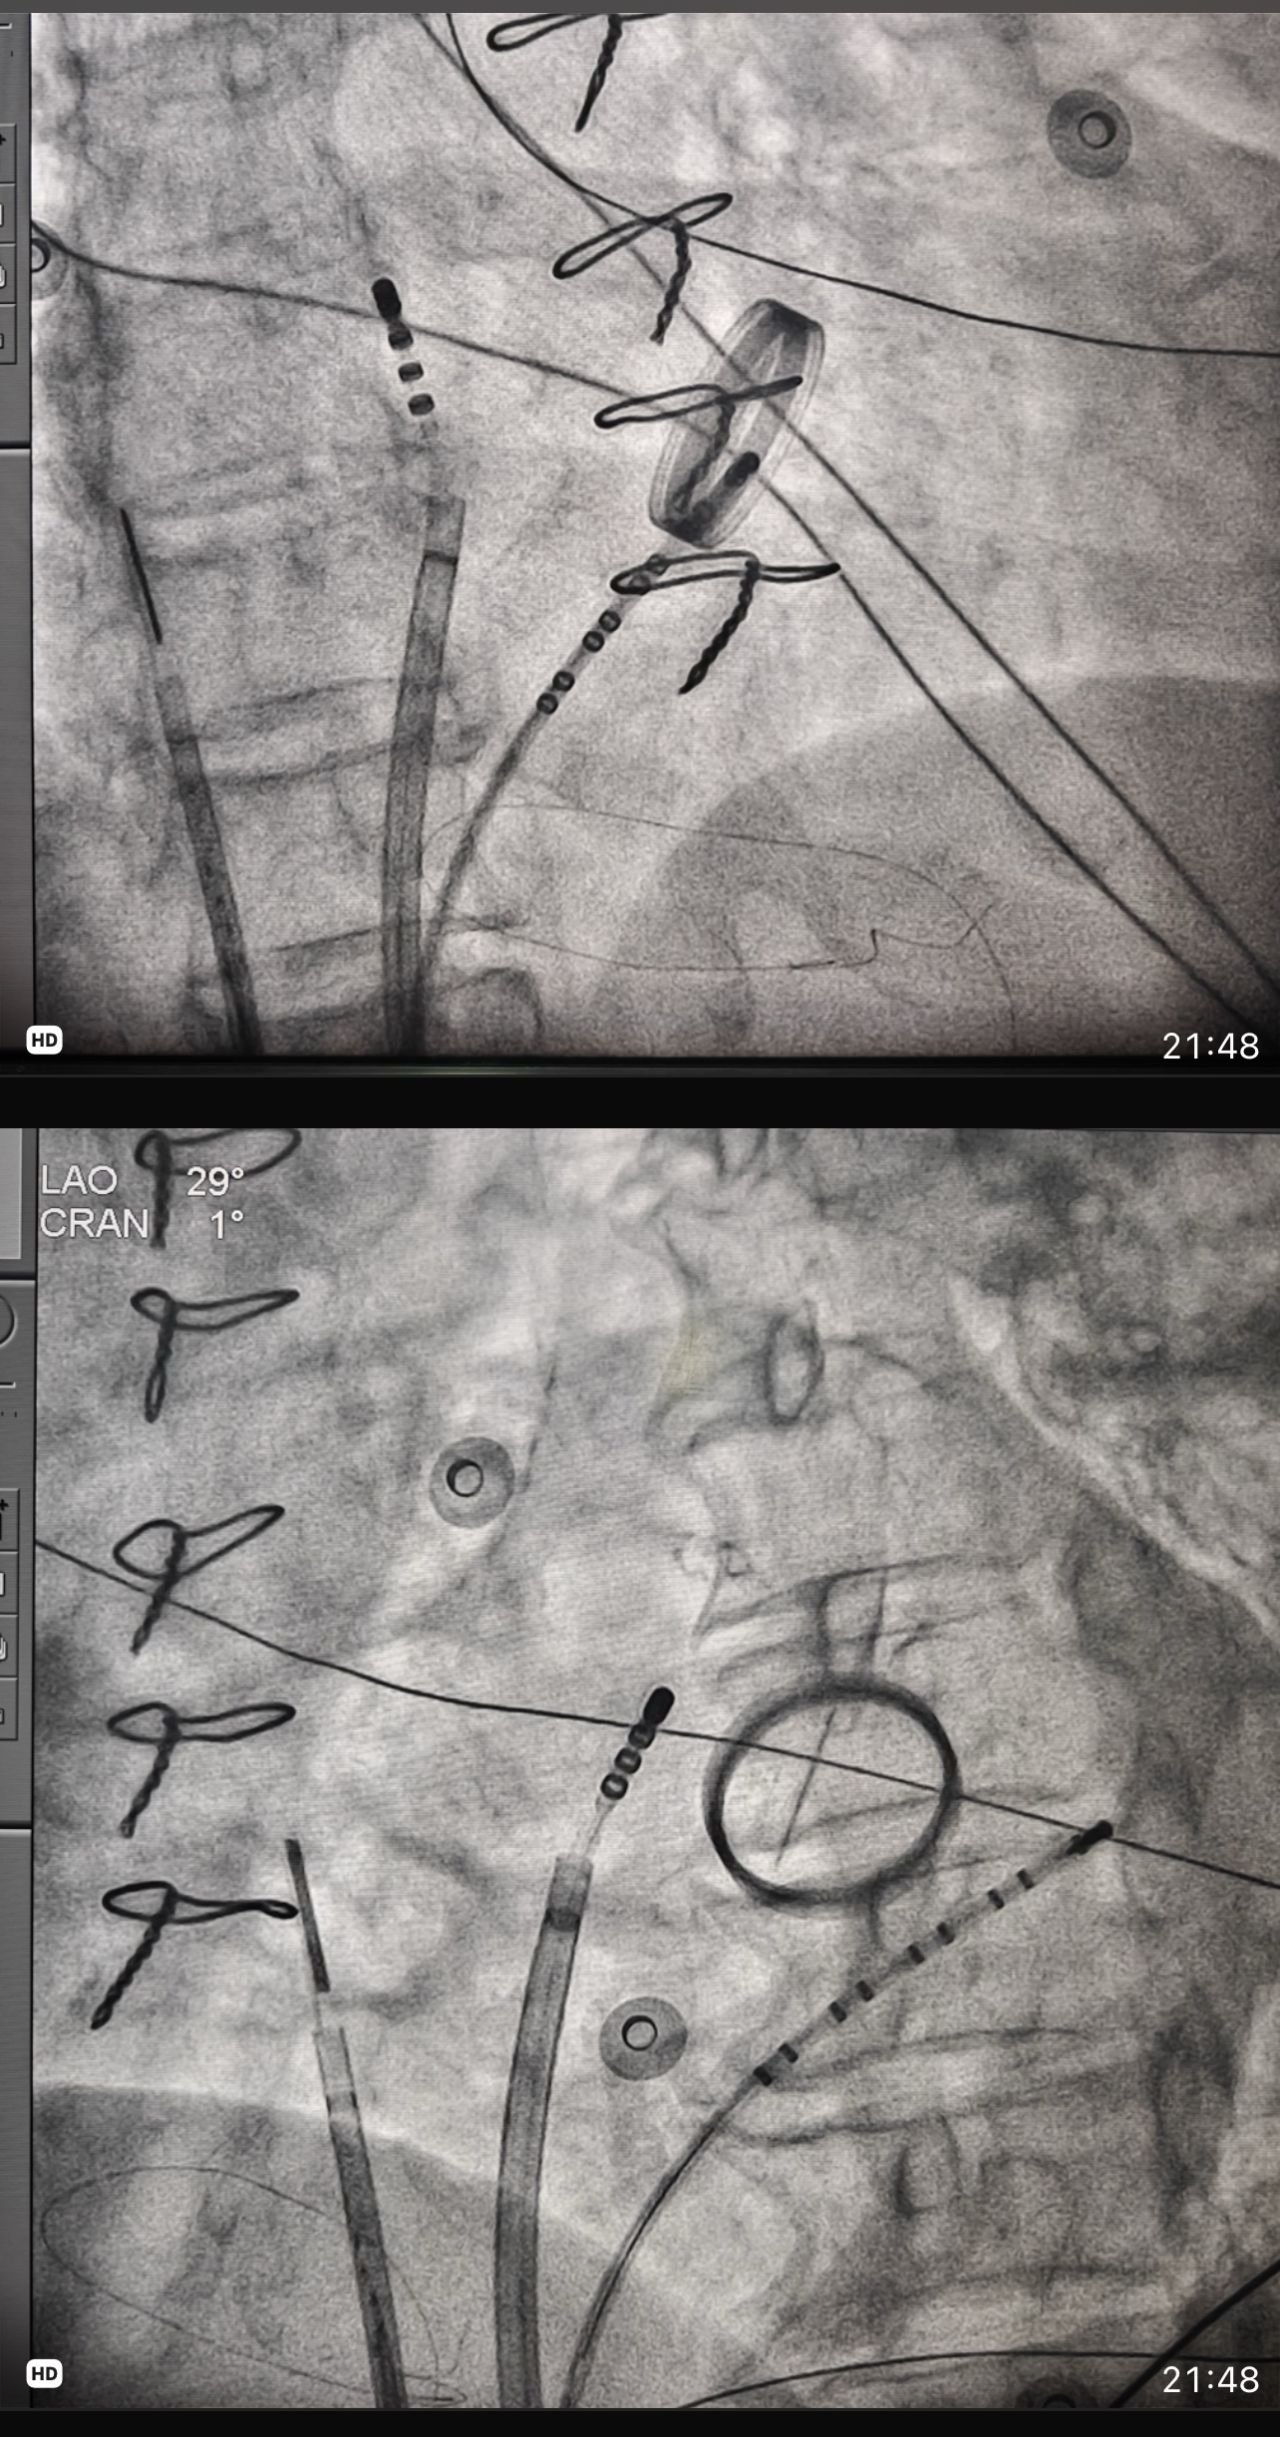

Published in: Blog PROCTOR AT ALMA MATER PROCTOR AT ALMA MATER – It’s always heartening to come back to your ALMA MATER and be a part of it’s milestone : helped start the Leadless pacing therapy at medical College Trivandrum.